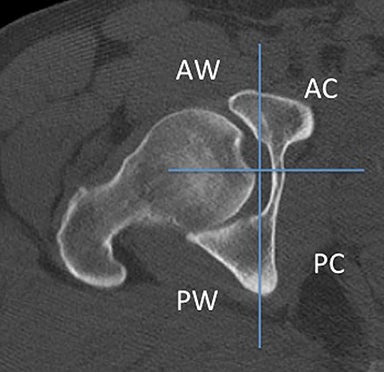

يقع الحُقّ على الجزء السفلي الوحشي من الحوض، ويتكون من التقاء ثلاث عظام هي: الحرقفة، الإسكي، والعانة. تشريحياً، يتألف الحُقّ من عامودين رئيسيين:

العمود الأمامي: يمتد من الشوكات الحرقفية الأمامية حتى فروع العانة.

العمود الخلفي: يمتد من الثلمة الوركية إلى عظم الإسكي.

يشكل العامودان معاً هيكلاً يشبه حرف Y المقلوب، وتشكّل هذه البنية أساس تصنيف ونمط إصابات الحُقّ.

يعتمد التصنيف الأكثر شيوعًا وهو Judet & Letournel على تقسيم الكسور إلى:

1. كسور أولية (Elementary):

الجدار الخلفي

العمود الخلفي

الجدار الأمامي

العمود الأمامي

الكسر المستعرض